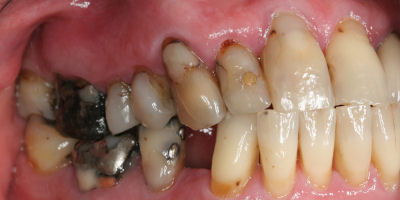

Before/After